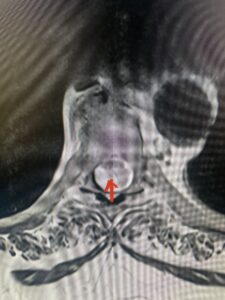

Fig 2a Sagittal and axial T2 weighted cervical MRIs demonstrating large C4 5 herniated disc with spinal cord compression red arrows

This 47-year-old male who four months prior was lifting weights developed sharp pain in his neck. After that he developed progressive numbness in his arms, neck pain and headache. He said that the right arm was worse than the left. On examination the patient had long tract weakness on the right side which included his triceps, finger extensors, hip flexors, and dorsiflexors. The patient did not have hyperreflexia. MRI (Fig. 2) demonstrated a massive, extruded disc herniation with severe cord compression. The patient because of progressive myelopathy and spinal cord compression was indicated for anterior cervical discectomy and fusion at C4-5 (Fig. 3). Patient had significant improvement of weakness and numbness post operatively.

Fig. 2a Sagittal T2-weighted cervical MRI demonstrating large C4-5 herniated disc with spinal cord compression (red arrow)

Fig: 2b Axial T2-weighted cervical MRI demonstrating spinal cord compression from C4-5 herniated disc (red arrow)